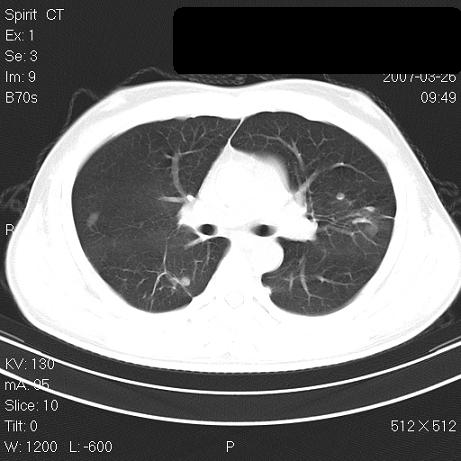

标题: CT7171B:补充治疗后2周复查 [打印本页]

标题: CT7171B:补充治疗后2周复查

治疗后2周复查,请讨论

结合以前的ct片,还是考虑肺挫伤,吸收多了。

支持:创伤性湿肺。现肺挫裂伤(出血 积气)大部分吸收。建议继续治疗!

结合以前的ct片,支持创伤性湿肺。现大部分吸收。

支持:创伤性湿肺、肺挫裂伤。现肺挫裂伤(出血、渗出、液气腔)大部分吸收。建议继续治疗!

支持:创伤性湿肺、肺挫裂伤。现肺挫裂伤(出血、渗出、液气腔)大部分吸收.

结合老片支持创伤性湿肺、肺挫裂伤。

经治疗后病灶明显吸收,考虑创伤性湿肺、肺挫裂伤